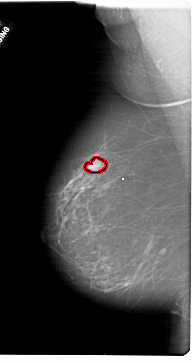

FILE: A_1778_1.LEFT_CC.OVERLAY

TOTAL_ABNORMALITIES 1

ABNORMALITY 1

LESION_TYPE MASS SHAPE LOBULATED MARGINS CIRCUMSCRIBED

ASSESSMENT 4

SUBTLETY 5

PATHOLOGY BENIGN

TOTAL_OUTLINES 1

BOUNDARY